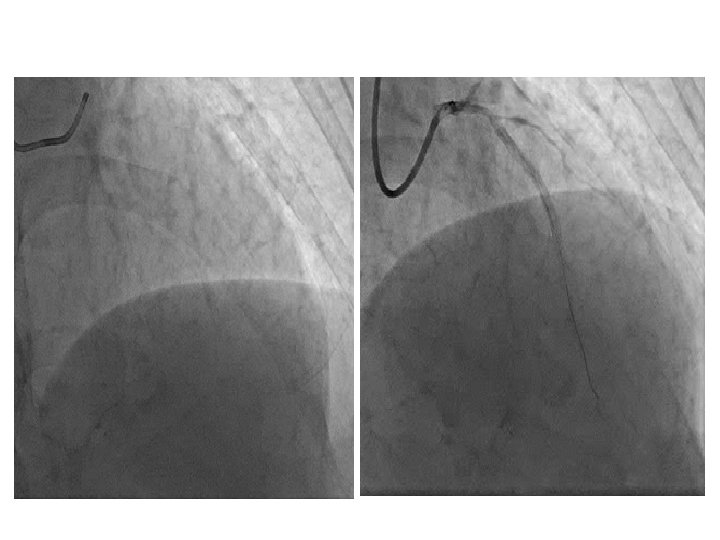

Пациент Б. , 58 лет Направление: диагностика ИБС

Пациент Б. , 58 лет Направление: диагностика ИБС